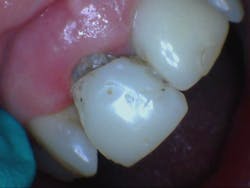

The implant system used was Straumann. The access point was on the lingual...somewhere...so, I just went for it. I drilled, and drilled, and drilled, and after 12 mm of making my way through resin (talk about a pain!), I found the tiiiiiny piece of Teflon that was covering the screw, but I couldn’t get it out! Since there was a void on the buccal, I was able to pull it out through the coping where the resin had broken off. I know...totally unconventional, but it worked! I was finally able to lock the driver in and release the implant (figure 3).

Figure 3: Temporary once removed